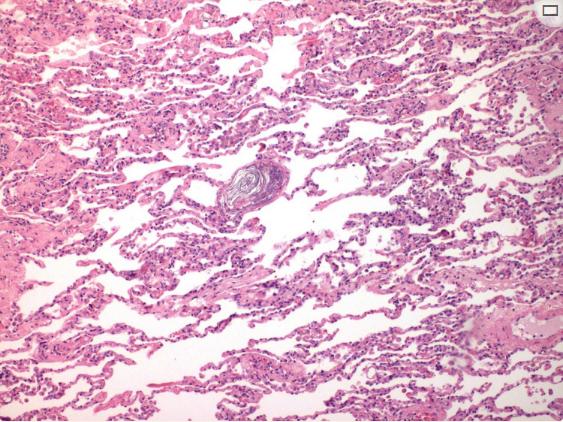

根据母亲的尸检,多器官组织病理学检查结果显示出血和炎症浸润、水肿、无定形嗜酸性物质以及中小血管中的纤维蛋白沉积,提示DIC(图1)。肺血管中出现粘液、胎儿上皮鳞片和胎粪提示ASP诊断(图2)。还存在含铁血黄素颗粒。子宫颈出现多个印痕,这证实了多处脐带缠绕。

图1、病例1小血管腔内发现纤维蛋白血栓(放大400倍)